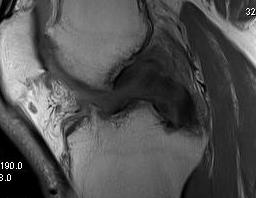

Sagittal MRI demonstrating complete tear of ACL and PCL

Sagittal MRI demonstrating complete tear of ACL and mid substance tear of PCL